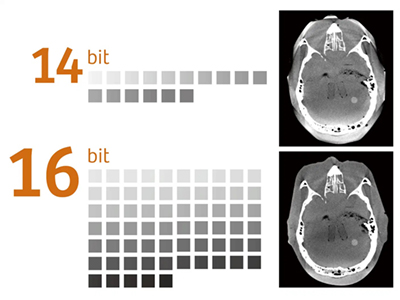

Artis zee i は,16bit の階調度を持つHDRフラットディテクタを搭載。グレースケールの階調が従来の4 倍に向上し,2Dイメージ,3Dイメージのクオリティがさらに高まりました。